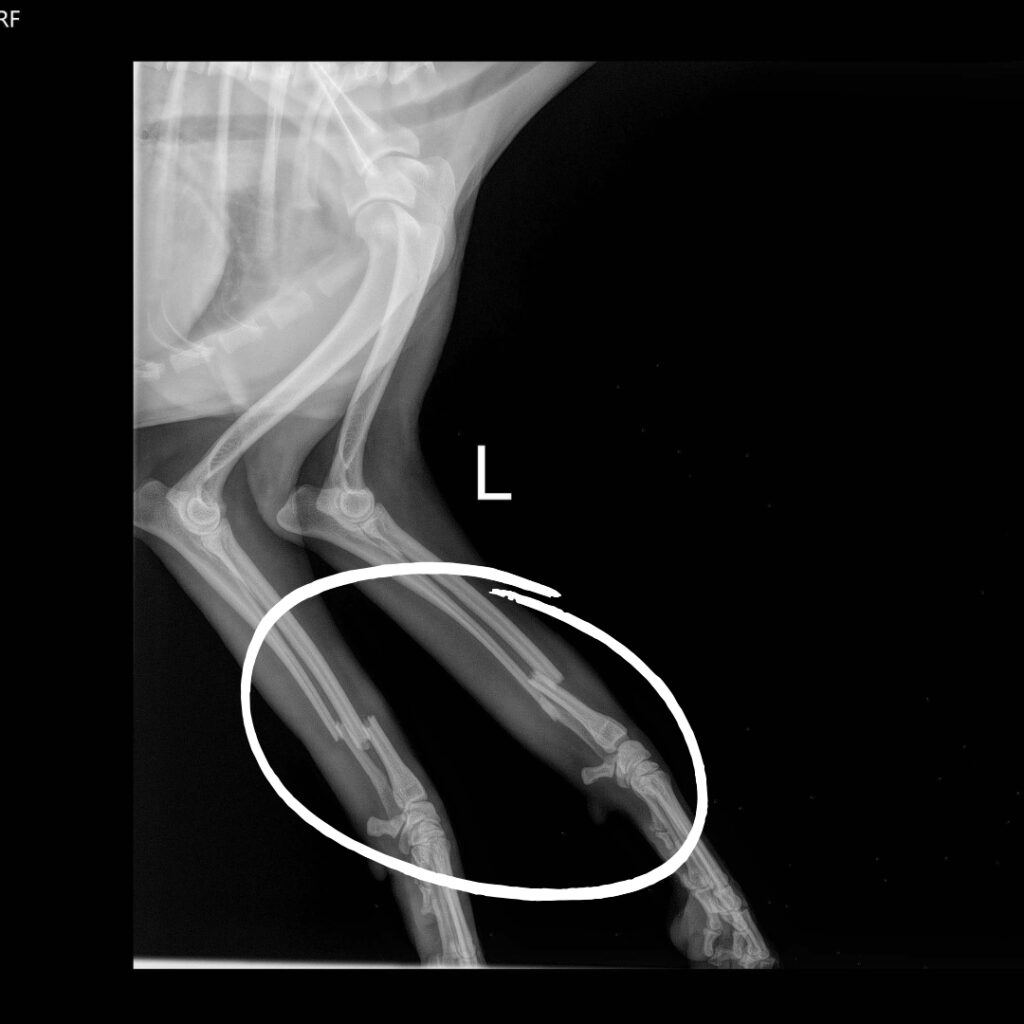

Riga Tony recently arrived at our Sam Swope Pet Treatment and Lifesaving Center in desperate need of our help after being hit by a car. He was clearly injured and unable to bear weight on either of his front legs without whining in pain. Our hearts broke for this poor two-year-old pup, so we welcomed him with open arms and promised to help as best as we can. We provided Riga Tony with medication to help him find relief and keep any potential infections from setting in, before taking several x-rays. Our worst fears were quickly confirmed: both of Riga Tony’s front legs are broken in two places.

Riga Tony’s recovery won’t be quick or easy. We’ve splinted his injuries, and have called a specialist who will soon determine if they can help this sweet pup make a full recovery without needing an amputation. Amputation surgery may still be necessary in the future, but our hope is that he will be able to keep at least one of his front legs when all is said and done. For now, Riga Tony is resting under our vet team’s watchful eyes. We will keep you posted on his progress but in the meantime, please donate to support lifesaving medical care for vulnerable animals just like Riga Tony.